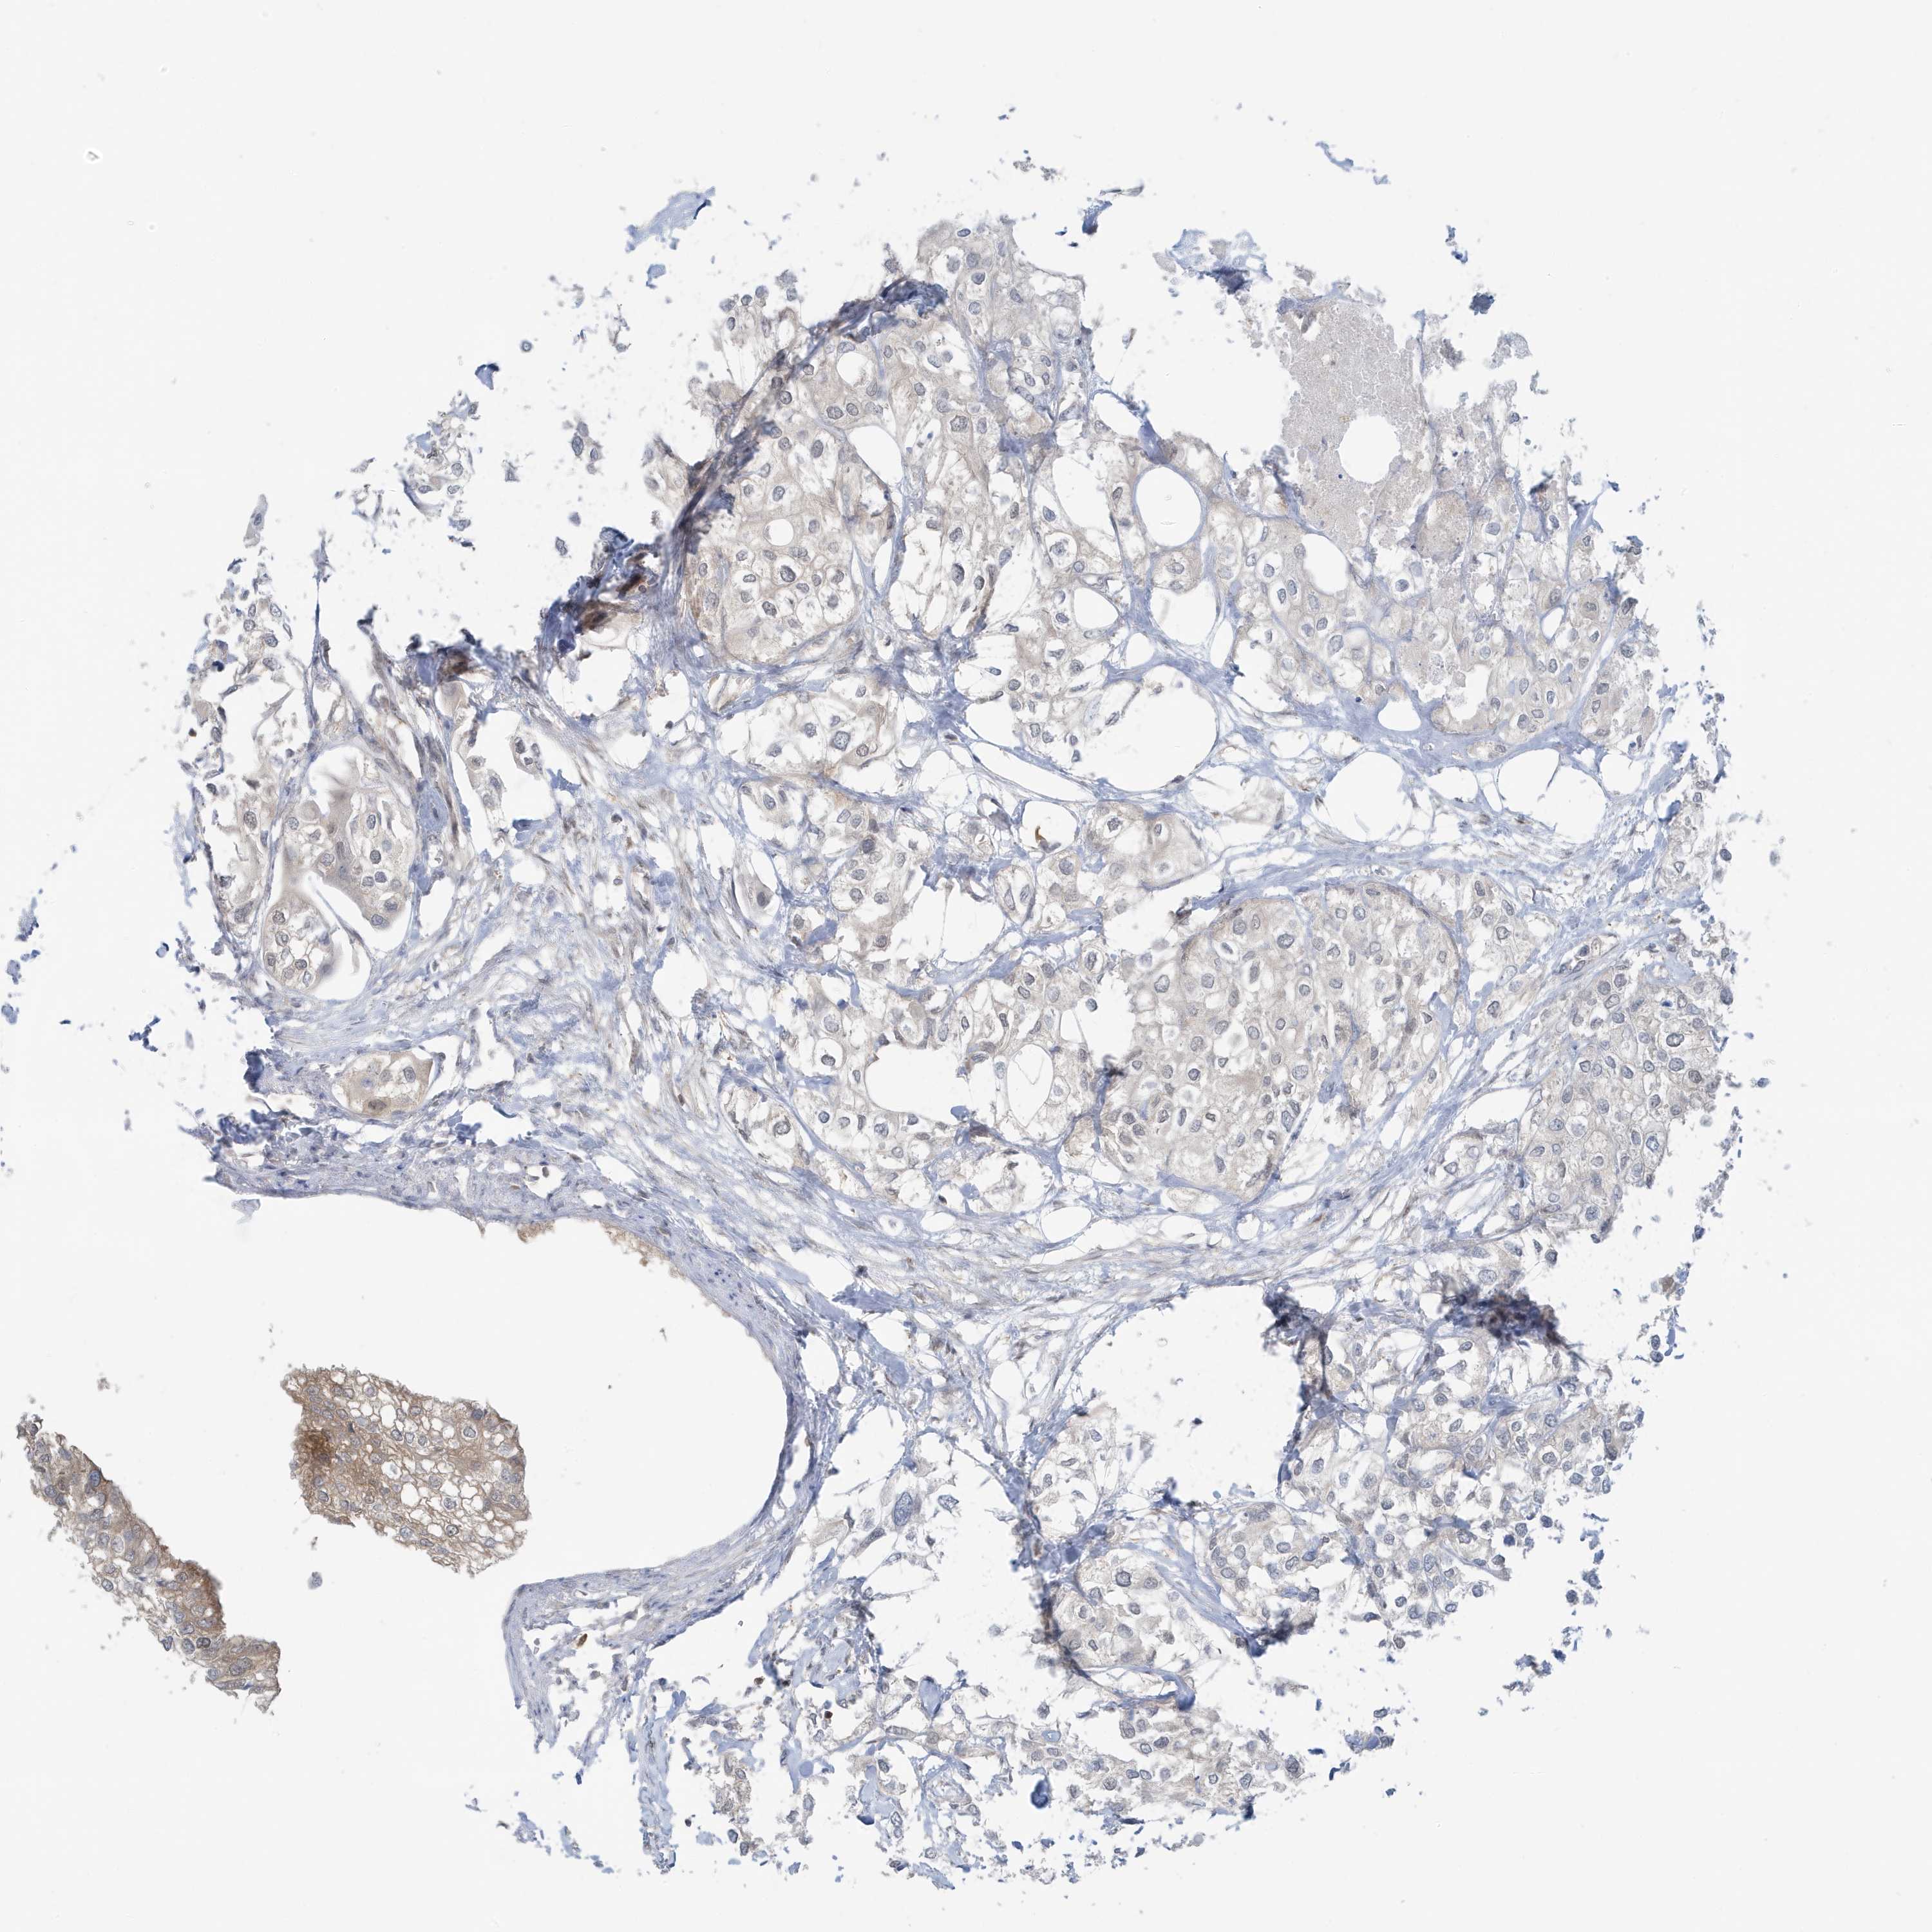

UROTHELIAL CANCER - Protein expressioni

A mouse-over function shows sample information and annotation data. Click on an image to view it in a full screen mode. Samples can be filtered based on level of antibody staining by selecting one or several of the following categories: high, medium, low and not detected. The assay and annotation is described here.

Antibody stainingi

Antibody staining in the annotated cell types in the current human tissue is reported as not detected, low, medium, or high, based on conventional immunohistochemistry profiling in selected tissues. This score is based on the combination of the staining intensity and fraction of stained cells.

Each image is clickable and will lead to virtual microscopy that enables deeper exploration of all samples and also displays staining intensity scores, fraction scores and subcellular localization as well as patient and tissue information for each sample.

Antibody HPA036141

Staining

High

Medium

Low

Not detected

Intensity

Strong

Moderate

Weak

Negative

Quantity

>75%

75%-25%

<25%

None

Location

Nuclear

Cytoplasmic/membranous

Cytoplasmic/membranous,nuclear

Urothelial carcinoma, Low grade

Urothelial carcinoma, High grade